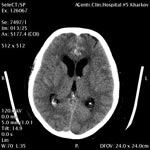

Ишемический инсульт Ишемический инсульт

Пациент Б., 50 лет

Cубарахноидально-паренхиматозное кровоизлияние.

ЦКБ5 Южной железной дороги, отделение лучевой диагностики.

В передних отделах межполушарной щели, субарахноидально, начиная от основания мозга, большое количество крови. Гиподенсивный очаг без четких контуров с наличием геморрагичекого фрагмента в колене мозолистого тела. В правой лобной доле паравентрикулярно гематома с перифокальным отеком. Небольшое количество крови в боковых, третьем, IV желудочках и сильвиевом водопроводе. Желудочки мозга обычной формы, расширены (ширина III желудочка - 7мм, передних рогов боковых: правого 11 мм, левого 12 мм). Конвекситальные подпаутинные пространства не расширены. Цистерны мозга не расширены. Костно - деструктивные изменения не определяются.